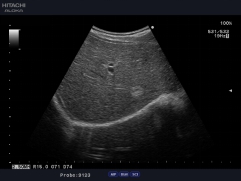

阿凡達采用多譜勒超聲成像技術(shù)和高精度數(shù)字波束形成技術(shù),融合組織諧波成像、斑點抑制、多波束并行等先進的圖像處理技術(shù)和高效的全數(shù)字圖文管理系統(tǒng)、輕松獲得更清晰的超聲圖像,專業(yè)化的測量軟件包可充分滿足臨床各種定量分析需求,靈活的配置和完全人體工學(xué)設(shè)計,提升了醫(yī)生臨床診斷的信心和臨床檢查的效率。

精確三維(3D)成像系統(tǒng)

全數(shù)字精確三維(3D)成像系統(tǒng),采用探頭陣元切割掃描,采集大量

精確地三維數(shù)據(jù),快速生產(chǎn)高分辨率、高清晰度的精確三維圖像,更

好的進一步測量和診斷。